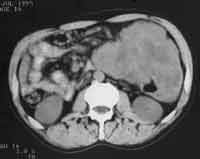

Рис. 5. Рак верхней трети нисходящей кишки (стрелка): неравномерное утолщение стенок кишки, их регидность, инфильтрация окружающей клетчатки в виде тяжей с вовлечением переднего листка околопочечной фасции, наличие признаков кишечной непроходимости.

Рис. 6. Массивная опухоль по периферии нисходящей кишки неотграниченная от ее стенок.